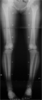

Tibia deformity-post lengthening on 14 years old chinese girl

Pre

Op

LEG LENGTH DISCREPANCY

▪ Left femur 1.3cm shorter

▪ Left tibia 2.5cm shorter